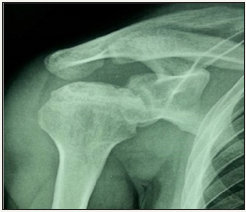

Figure 3:True anterior-posterior (AP) view in case 2: the subchondral sclerosis and radiolucent area in humeral head.

Radiographic evaluation: Standard radiological diagnoses include conventional x-ray images. True anterior-posterior (AP) view (Figure 3) revealed subchondral sclerosis and a radiolucent area in humeral head. Also, there were some degenerative changes in the articular surface of humeral head. MRI determined the avascular necrosis of humeral head (Figure 4).